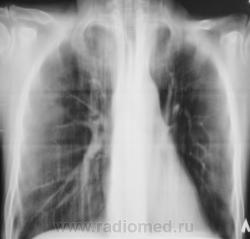

Следущий "контроль".

А сейчас, если не ошибаюсь, есть свежие очаги слева?

Я тоже отметил "свежие" очаги, но они появились на "фоне" курса лечения.

А на томограмме это очаги?

Мы трактовали это как крупноочаговые тени.